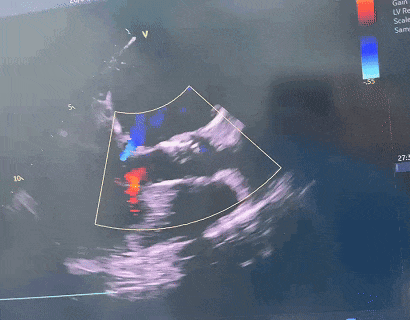

超声评估